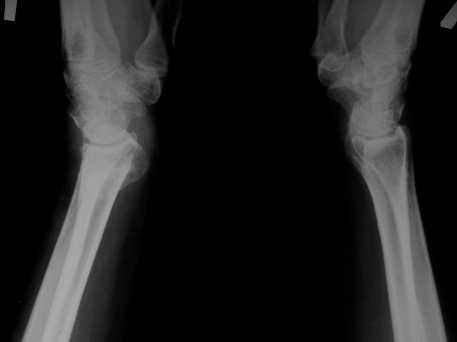

Уважаемые коллеги! Обратилась женщина, 55 лет. Травма 3 месяца назад, лечилась по месту жительства (Рис.1). Косорукость, боли, ограничение движений.

Досняли - рис.2-6. Хотелось-бы услышать мнения об объеме операции. С уважением, Юрий Алексеевич Булахтинглавный травматолог Камчатского Военно-морского госпиталя

u pazientki po nauchnomu ulna abutment/impingment syndrome posle posttraumaticheskogo ukorochenia radiusa

na rengene znachitelnoe ukorochenie radiusa, sustavnaia poverchnost naklonena dorsalno chresmerno , chetko vidno nekongruentnost DRUJ - distalnogo radioulnarnogo sustava ,ulna prosto vtikaetsia v triquetrum .